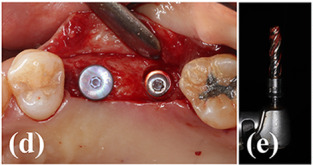

Case photos provided by: Polycaprolactone Impregnated 3D Printed Nanohydroxyapatite for Sinus Augmentation: A Randomized Controlled Trial

Clinical photographs of the surgery. (a) A bony access window was created on the lateral wall of the maxillary sinus. (b) 3DPHA‐PCL was filled in the sinus after detaching the sinus membrane. (c) A collagen membrane was applied to cover the access window. (d) Dental implants were placed on #15 and #16 areas. (e) A bone core biopsy was performed during drilling. (f) The obtained specimen. (g) An implant prosthesis was delivered (#17 was extracted).